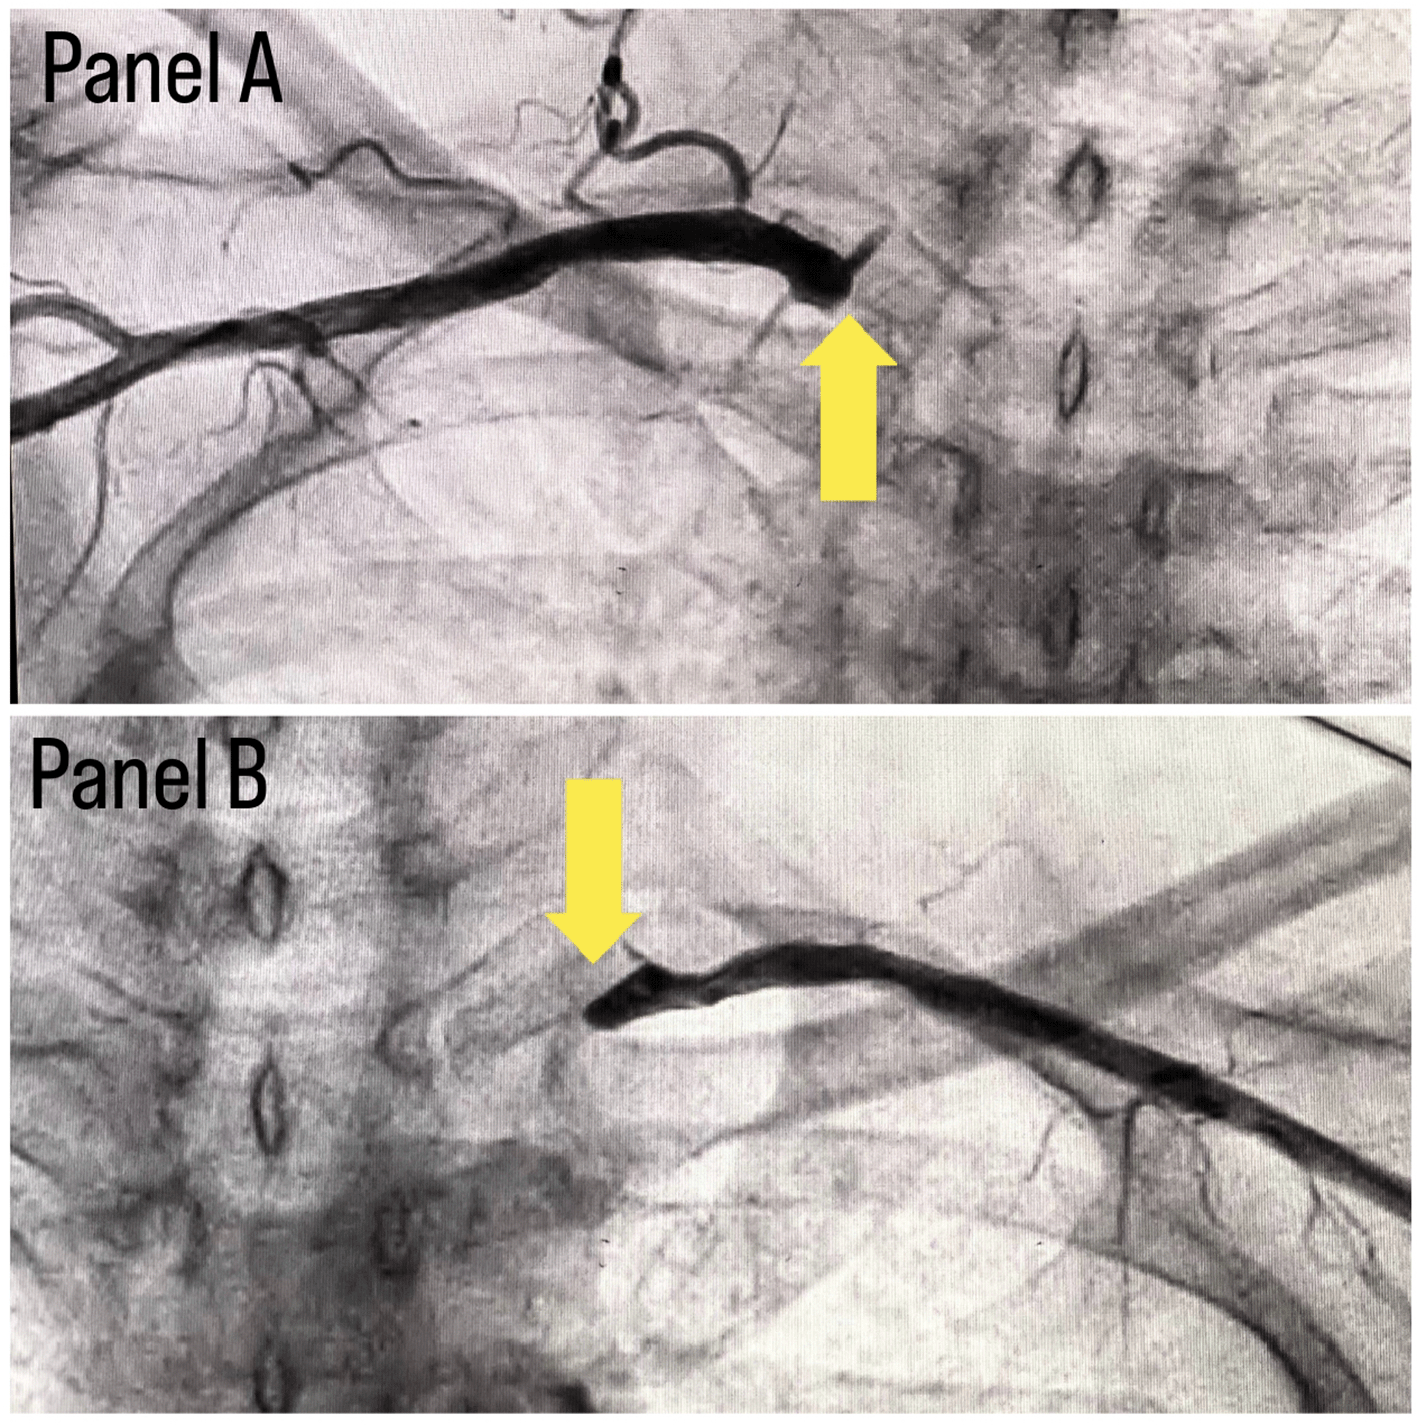

Coronary angiography was done and a triple vessel coronary artery disease was diagnosed as shown in Figure 1. A subclavian puncture was taken to look for a subclavian artery considering the claudication symptoms of the patient and peripheral vascular disease was diagnosed with bilateral subclavian artery stenosis as shown in Figure 2. Considering the severity of claudication pain in our case, bilateral renal and femoral arteries were also checked via aortic flush and bilateral renal artery ostial stenosis was seen, as shown in Figure 3, while the femoral arteries appeared normal bilaterally.